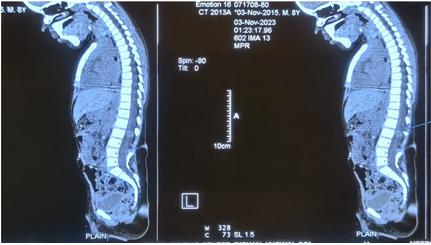

脊柱MRI显示硬膜内结节状病变(图2)在L2水平脊髓栓系的椎管后部,脊髓纵裂的特征(图3)和L4-5水平的背侧真皮窦,有脊髓栓系。CT扫描(图4)显示在L2、L3、L4、L5的后弓中的缺陷,以及在椎管、椎骨中的所有骶骨溶胶,在右侧L4/5小关节中注意到的部分融合,以及在椎管和L4/5水平的皮肤之间注意到的细的线性纤维化样束,可能是真皮窦。对颅脊髓轴进行筛查以排除脑积水和Arnold-Chiari畸形。根据临床和放射学表现,患者被安排手术。手术通过背部腰部区域的中线皮肤切口进行。暴露后,被证实为I型脊髓分裂畸形(SCM),硬膜外骨刺位于D12-L2椎骨水平。每个半索都有自己的硬膜囊和独立的脂肪脊髓脊膜膨出。使用高速钻在硬膜外显微镜下切除骨刺。硬脑膜以倒置的Y形方式打开。通过使用细致的显微神经外科解剖,对白线(脂肪瘤组织和脐带组织之间的界面)进行脂肪瘤组织的切除和脐带的解开。患者接受了脊髓松解术,同时切除了髓外硬膜内皮样肿块和脂肪瘤(图5和6)。术中模拟对肛周括约肌和下肢肌肉没有产生显著的反应。该患者接受了术中体感和运动诱发电位神经监测,未发现诱发电位间歇性降低。肿块的病理显示皮样囊性病变。

图4、患者的CT扫描显示L2-5后弓缺损,椎管内骶骨占位性病变